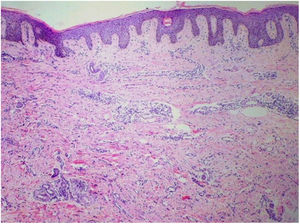

Punch biopsies of the skin lesions were performed, which showed a normal epidermis and fibrohistiocytic proliferation with small vessels in the reticular dermis, displaying lumen vessels filled with prominent endothelial cells, involved with a perivascular inflammatory response composed by multinucleated histiocytic cells (MCs) and a few plasma cells. In the papillary dermis, fibroblastic proliferation and thickened collagen fibers were found (Figs. 2 and 3) and numerous bizarre MCs with scalloped margins were found in the adjacent dermis. The immunohistochemical (IHC) panel performed found the following: S-100 protein (negative), FXIIIa (positive) in MCs, CD68 (positive) in MCs, CD34 and CD31 (positive) in small vessels, and CD4 (positive) in dermal lymphocytes (Figs. 4 and 5). The final diagnosis was established as compatible with multinucleate cell angiohistiocytoma. Due to the benign nature of the illness, the patient chose not to undergo treatment.

The main histopathological finding in MCAH is the proliferation of venules and capillaries in the dermis, accompanied by lymphocytic infiltrate and angular multinucleated cells. These cells may exhibit up to ten hyperchromatic nuclei and have basophilic cytoplasm; the cells express vimentin and factor XIIIa, and there is dermal fibrosis and sparse lymphohistiocytic infiltrate.2,7,10